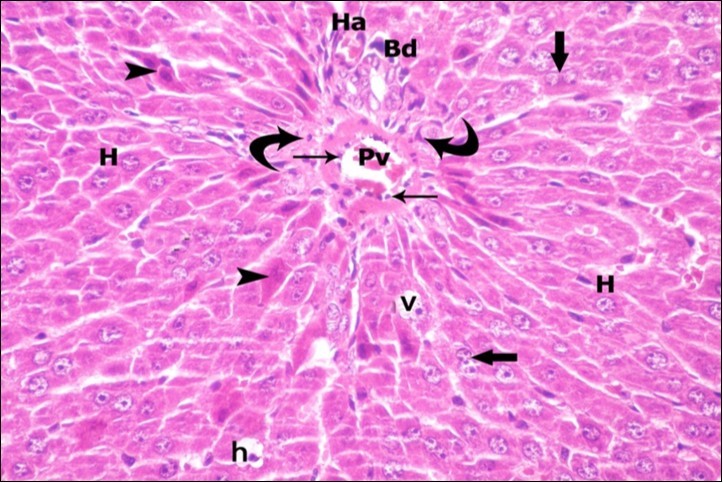

Examination of H&E stained sections of the 1st group (control group) revealed hepatic architecture of tightly packed cords of hepatocyte with vesicular nuclei and acidophilic cytoplasm radiating from the central vein (Figure 1). Portal area was composed of a portal vein, branch of hepatic artery and bile duct lined by single cuboidal cells with dark rounded nuclei. Blood sinusoids with their endothelial lining of Kuppfer cells were noticed in between hepatic cords (Figure 2). Examination of the liver sections of the 2nd group (vitamin E treated group) showed nearly the same histological features as the 1st group. The 3rd group (ZnONPs-treated group) showed a marked loss of the normal liver arrangement with dilated congested central veins and blood sinusoids. Most of hepatocytes had large cytoplasmic vacuoles and darkly stained nuclei other hepatocytes were ballooned (Figure 3). The portal area showed dilated congested portal vein with proliferation of bile duct, necrotic foci in between the hepatocytes with inflammatory cellular infiltration (Figure 4). The portal area showed also elongation of the endothelial lining of dilated congested portal vein and increasing amount of connective tissue fibers (Figure 5). There was congested hepatic artery with increasing thickness of its muscular layer (Figure 6). Bile duct showed proliferation with stratification of its epithelial lining (Figure 7).

Figure 1.A photomicrograph of a section in the liver of a control adult albino rat showing polygonal hepatocytes (H) radiating from central vein (Cv) with rounded vesicular nuclei and acidophilic cytoplasm. Narrow radiating blood sinusoids (s) in between liver cords and their lining endothelium are noticed. Binucleated cell is also seen (thick arrow). (H&E X400)

Figure 2.A photomicrograph of a section in the liver of a control adult albino rat showing portal area containing bile duct (Bd) and hepatic artery (Ha). Polygonal hepatocytes (H) with rounded vesicular nuclei and acidophilic cytoplasm can be observed. Narrow radiating blood sinusoids (s) in between liver cords and their lining endothelium are seen. Binucleated cells are also seen (thick arrows). (H&E X400)

Figure 3.A photomicrograph of a section in the liver of ZnONPs-treated adult albino rat showing dilated congested central vein (Cv) and ballooning of hepatocytes (double arrows) with darkly-stained nuclei (h) and vacuolated cytoplasm (v). Binucleated cells are also seen (thick arrows). (H&E X400)

Figure 4.A photomicrograph of a section in the liver of ZnONPs-treated adult albino rat showing dilated congested portal vein (Pv), proliferation of bile duct (Bd), inflammatory cell infiltration (IF) and ballooning of hepatocytes (double arrows) with darkly-stained nuclei (h) and vacuolated cytoplasm (v). Area of necrotic focus is also present (star). (H&E X400)

Figure 5.A photomicrograph of a section in the liver of ZnONPs-treated adult albino rat showing congested portal vein (Pv) with elongation of its endothelial lining (arrow head) and increasing amount of connective tissue fibers (Cf). Mononuclear cellular infiltration (IF) and hepatocytes with darkly-stained nuclei (h) and vacuolated cytoplasm (v) could be demonstrated. (H&E X400)

Figure 6.A photomicrograph of a section in the liver of ZnONPs-treated adult albino rat showing congested hepatic artery (Ha) with increasing thickness of its muscular layer (M) and proliferation of bile duct (Bd). Mononuclear cellular infiltration (IF), congested blood sinusoids (s) and hepatocytes with darkly-stained nuclei (h) and vacuolated cytoplasm (v) are also seen. (H&E X400)

Figure 7.A photomicrograph of a section in the liver of ZnONPs-treated adult albino rat showing proliferation of bile duct (Bd) with stratification of its epithelial lining (E). Mononuclear cellular infiltration (IF) in the portal area and hepatocytes with darkly-stained nuclei (h) and vacuolated cytoplasm (v) are also seen. (H&E X400)

Examination of H&E stained liver sections of the 4th group (ZnONPs &VE-treated group) showed variable degrees of improvement with slightly preserved liver architecture when compared to that of the ZnONPs-treated group. Some hepatocytes showed vacuolated cytoplasm while, others had vesicular nuclei and acidophilic cytoplasm; many cells were binucleated and slightly dilated blood sinusoids (Figure 8). The Portal area showed less dilated portal vein with marked reduction in cellular infiltration in comparison with ZnONPs-treated group (Figure 9).

Figure 8.A photomicrograph of a section in the liver of ZnONPs & VE- treated adult albino rat showing slightly dilated sinusoids (s) and central vein (Cv) with flat endothelial lining (thin arrows). Most of hepatocytes are with vesicular nuclei and acidophilic cytoplasm (H). Others show darkly-stained nuclei (h) and less vacuolated cytoplasm (v). Binucleated cells (thick arrows) are also seen. (H&E X400)

Figure 9.A photomicrograph of a section in the liver of ZnONPs & VE- treated adult albino rat showing portal area; portal vein (Pv) with flat endothelial lining (thin arrows), bile duct (Bd) and hepatic artery (Ha). Few inflammatory cells are observed (curved arrows). Most of hepatocytes with vesicular nuclei (H) show strong acidophilic cytoplasm (arrow head), some hepatocytes with darkly-stained nuclei (h) and vacuolated cytoplasm (v). Binucleated cells (thick arrows) are also seen. (H&E X400)